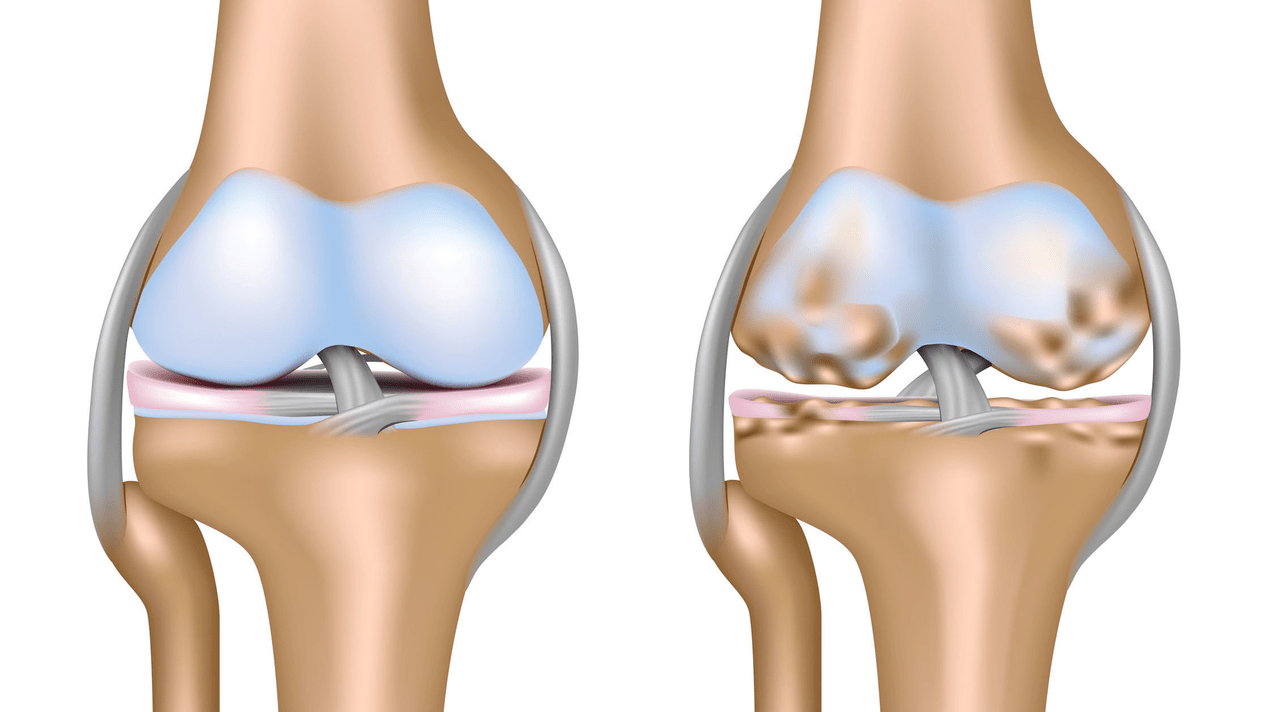

Arthrose de l'articulation du genou (gonarthrose) est une maladie chronique évolutive des articulations du genou avec lésions, amincissement et destruction de leur partie cartilagineuse (surfaces articulaires du fémur et du tibia) ainsi que des lésions de l'os sous-chondral. Des études (arthroscopie et IRM) ont montré qu'en plus des lésions du cartilage articulaire, les ménisques et la membrane synoviale sont également impliqués dans le processus. La gonarthrose est l'une des maladies orthopédiques les plus courantes. Il existe ses synonymes : arthrose (OA), arthrose déformante. La maladie représente un problème socio-économique important car elle est répandue et, en raison de la douleur constante, elle détériore considérablement la qualité de vie des patients et devient en outre une cause de niveaux élevés d'invalidité.

Jusqu’au milieu des années 1980, il n’existait pas de définition uniforme de la maladie. Ce n’est qu’en 1995 que le Comité d’arthrose de l’American College of Rheumatology a caractérisé la maladie comme le résultat de facteurs mécaniques et biologiques conduisant à un déséquilibre entre les processus de dégradation et de synthèse de la matrice extracellulaire du cartilage articulaire. En conséquence, une dégradation et une dégénérescence des fibres se produisent, des fissures, de l'ostéosclérose et un compactage de la couche corticale de l'os sous-chondral se produisent, des ostéophytes se développent et des kystes sous-chondraux se forment.

Le premier stade de la maladie est caractérisé par des modifications primaires du cartilage hyalin. Les structures osseuses ne sont pas affectées. L'apport sanguin dans les vaisseaux intra-osseux et les capillaires est perturbé. La surface du cartilage devient sèche et perd sa douceur. Si la maladie s'accompagne d'une synovite constamment tendue, un kyste de Baker (hernie bombée de la capsule articulaire de la région poplitée) se développe. Une douleur sourde survient après une forte tension sur l'articulation. Il peut y avoir un léger gonflement qui disparaît avec le repos. Il n'y a aucune déformation.

Gonarthrose, stade II

Au cours de la deuxième étape, la couche cartilagineuse devient considérablement plus fine et disparaît complètement à certains endroits. Des ostéophytes apparaissent sur les bords des surfaces articulaires. Les propriétés qualitatives et quantitatives du liquide synovial changent : il devient plus épais, plus visqueux, ce qui entraîne une détérioration de ses propriétés nutritionnelles et lubrifiantes. La douleur est plus longue et plus intense et un grincement se fait souvent entendre lors du mouvement. Il existe une restriction légère à modérée des mouvements et une légère déformation de l’articulation. Prendre des analgésiques aide à soulager la douleur.

Gonarthrose, stade III

Manque de cartilage dans la plupart des zones touchées, sclérose (durcissement) sévère de l'os, nombreux ostéophytes et rétrécissement ou absence sévère de l'espace articulaire. La douleur est quasi constante et la démarche est altérée. La mobilité est sévèrement restreinte et des déformations articulaires importantes se produisent. Les AINS, la physiothérapie et les autres méthodes standard de traitement de l'arthrose du genou sont inefficaces.